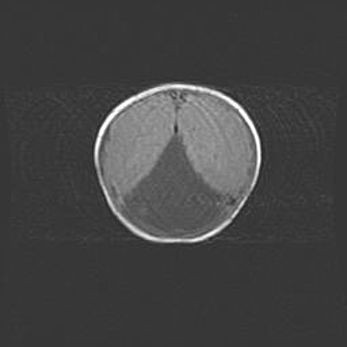

Мальформация Денди-Уокера. Киста задней черепной ямки.

Агенезия мозолистого тела.

Возраст: 2,5 месяца

Вес: 2420 г

Пол: женский

Окружность головы: 37 см

Срок гестации: 32 недели

Мальформация Денди—Уокера — редкий вид патологии ЦНС, представляющий собой врожденный порок развития каудального отдела ствола и червя мозжечка, ведущий к неполному раскрытию срединной (Мажанди) и латеральных (Лушка) апертур IV желудочка мозга. Для этогно синдрома характерна триада симптомов: гипотрофия червя мозжечка и/или полушарий мозжечка, кисты задней черепной ямки, гидроцефалия различной степени. В 70% случаев порок сочетается и с другими аномалиями головного мозга, в частности с агенезией мозолистого тела.